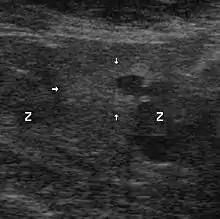

Échographie avec biopsies transrectales

Il n'existe actuellement aucun examen d'imagerie de pratique courante susceptible de détecter seul un foyer d'adénocarcinome prostatique avec une sensibilité et une spécificité satisfaisantes.

Contrairement à une idée encore largement répandue, et bien que cet examen soit ainsi encore souvent prescrit, l'échographie endorectale, seule, n'a pas d'utilité pour le diagnostic positif du cancer de la prostate, au regard du désagrément qu'elle est susceptible d'occasionner. Elle prend, en revanche, tout son intérêt lorsqu'elle sert à guider des biopsies prostatiques. Les autres modalités d'imagerie (scanner, IRM) ont un intérêt dans le bilan d'extension.

Technique

Une sonde d'échographie endorectale munie d'un guide d'aiguille est introduite dans le rectum. Les biopsies sont effectuées avec des aiguilles munies d'un mandrin encoché. Le mandrin pénètre le premier. L'aiguille vient le recouvrir, pour trancher et emprisonner ainsi le fragment de prostate situé dans l'encoche. Les mouvements du mandrin et de l'aiguille sont automatisés par un système de ressorts et le prélèvement est effectué en quelques centièmes de seconde. L'écran de l'échographe, muni d'un repère représentant le trajet de l'aiguille, permet, ainsi, des tirs biopsiques très précis.